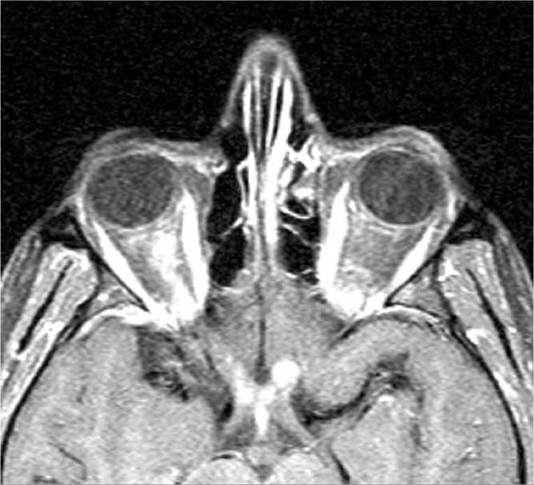

7. Computed tomography (CT) or magnetic resonance imaging (MRI) of the chest to evaluate lung apex for possible mass (e.g., Pancoast tumor).

8. MRI of the brain and neck.

9. .Magnetic resonance angiography (MRA) or CT angiography (CTA) of the head/neck to evaluate for carotid artery dissection (especially with neck pain). Obtain carotid angiogram if MRA or CTA yield equivocal results.